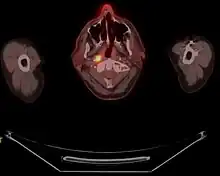

Staging

Staging of nasopharyngeal carcinoma is based on clinical and radiologic examination. Most patients present with Stage III or IV disease.

Stage I is a small tumor confined to nasopharynx.

Stage II is a tumor extending in the local area, or that with any evidence of limited neck (nodal) disease.

Stage III is a large tumor with or without neck disease, or a tumor with bilateral neck disease.

Stage IV is a large tumor involving intracranial or infratemporal regions, an extensive neck disease, and/or any distant metastasis. [16]

Stage T1 nasopharyngeal cancer

Stage T2 nasopharyngeal cancer

Stage T3 nasopharyngeal cancer

Stage T4 nasopharyngeal cancer